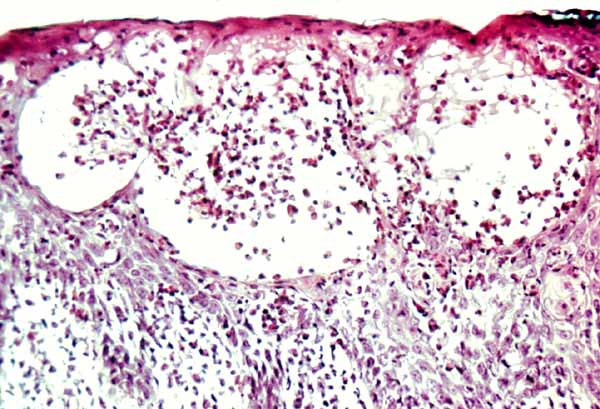

The vesicles seen during the first stage arise within the epidermis and are associated with spongiosis. They are of the type seen in dermatitis . However, they differ from the vesicles of dermatitis by the numerous eosinophils within them and around them in the epidermis (eosinophilic spongiosis) . The epidermis between the vesicles often shows single dyskeratotic cells and whorls of squamous cells with central keratinization. Like the epidermis, the dermis shows an infiltrate containing many eosinophils and some mononuclear cells.

The areas of pigmentation seen in the third stage show extensive deposits of melanin within melanophages located in the upper dermis. Usually, this dermal hyperpigmentation is found in association with a diminution of pigment in the basal layer, the cells of which show vacuolization and degeneration . In some cases, however, the cells of the basal layer contain abundant amounts of melanin .